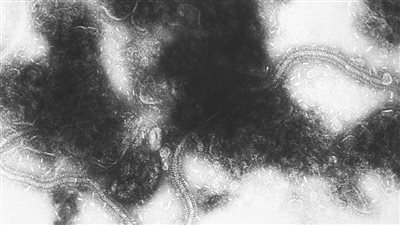

سادت حال من الجدل بسبب انتشار الفيروس التنفسي المخولي بين الأطفال، وذلك بعد مسحة قطاع الطب الوقائي بوزارة الصحة، والذي بينت أن 73% من الأطفال المصابين بالأعراض التنفسية، ثبت إصابتهم بالفيروس التنفسي المخلوي أو الغدي.